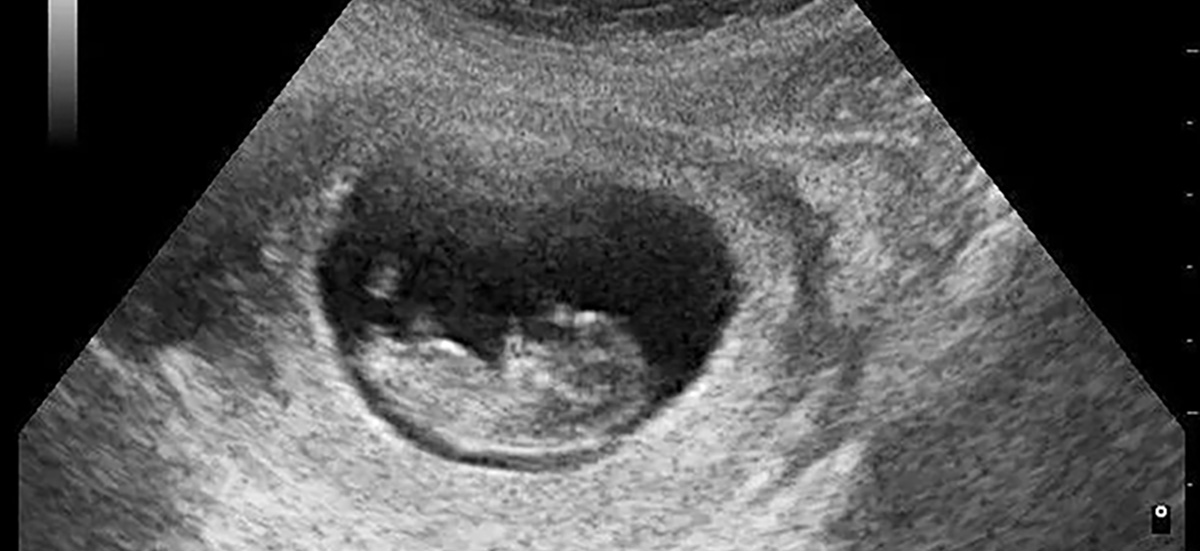

寶貝女兒降落地球